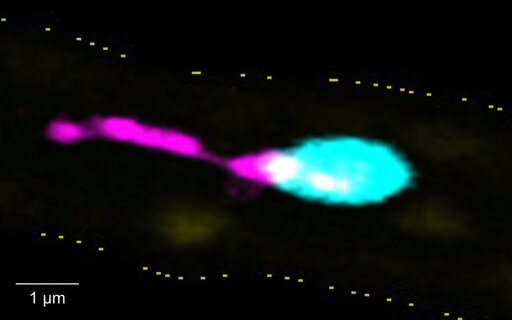

A team from Würzburg has fundamentally changed our understanding of platelet biology. The researchers demonstrate that the surface protein integrin αIIbβ3 is not only a key molecule in blood clotting, but can also act as a pro-inflammatory effector during severe disease processes. Under these conditions, αIIbβ3 switches function and becomes a structural component of a previously unknown organelle: PITT (platelet-derived integrin- and tetraspanin-rich tether).